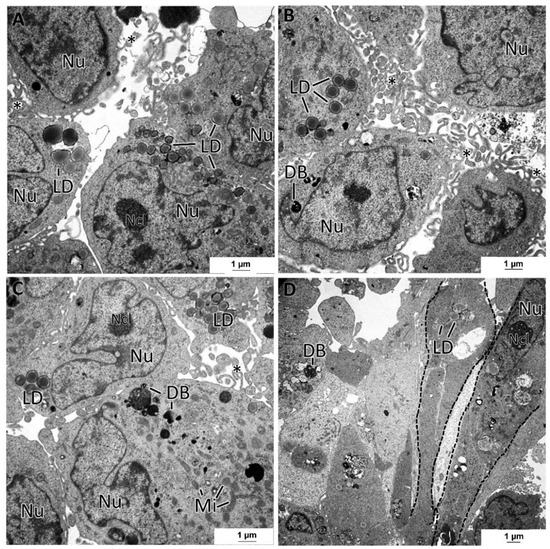

3.5. General Ultrastructure of MCAs